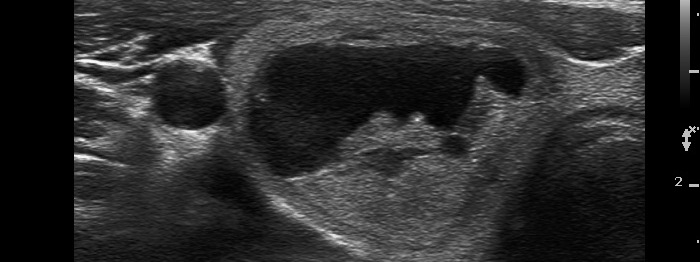

Papillary carcinoma (histological diagnosis) |

This case is less edifying or may be more edifying. Compared with the previous case, the granules here are less bright. Nevertheless, great proportion of them belong to punctate echogenic foci (arrows). It is worth to compare these with non-specific granules (arrowheads). |